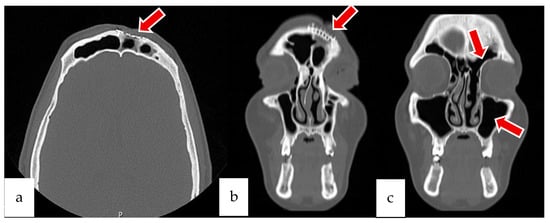

2.2. Case 2